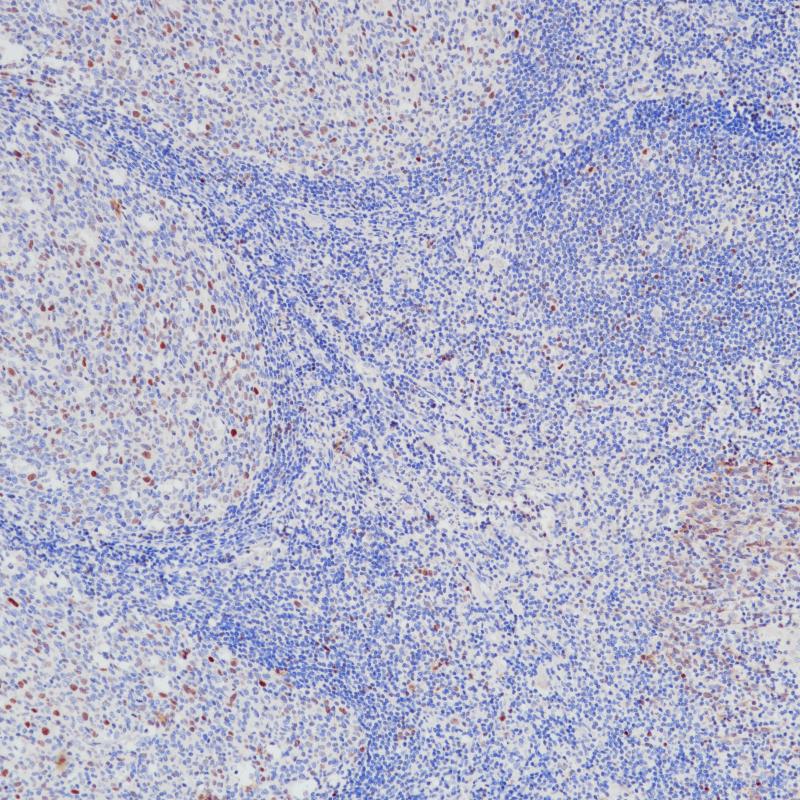

FABP3 重组兔单克隆抗体

阳性对照

心脏

亚细胞定位

细胞质